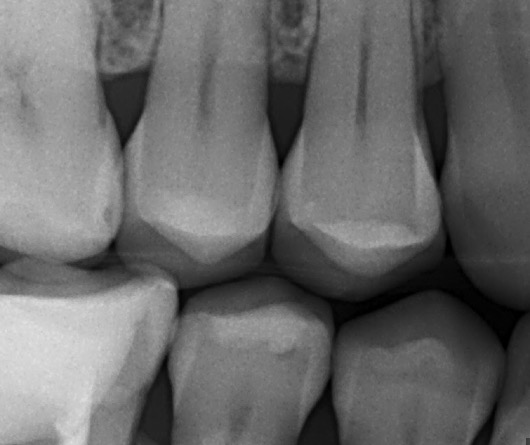

Volgens mijn oude tandarts is alles op deze foto in orde.

Mijn nieuwe tandarts ziet iets onder de vulling op de middelste kies onderaan, en wil dit weghalen.

Is dat echt nodig denkt u?

De foto is ongeveer een jaar geleden gemaakt.